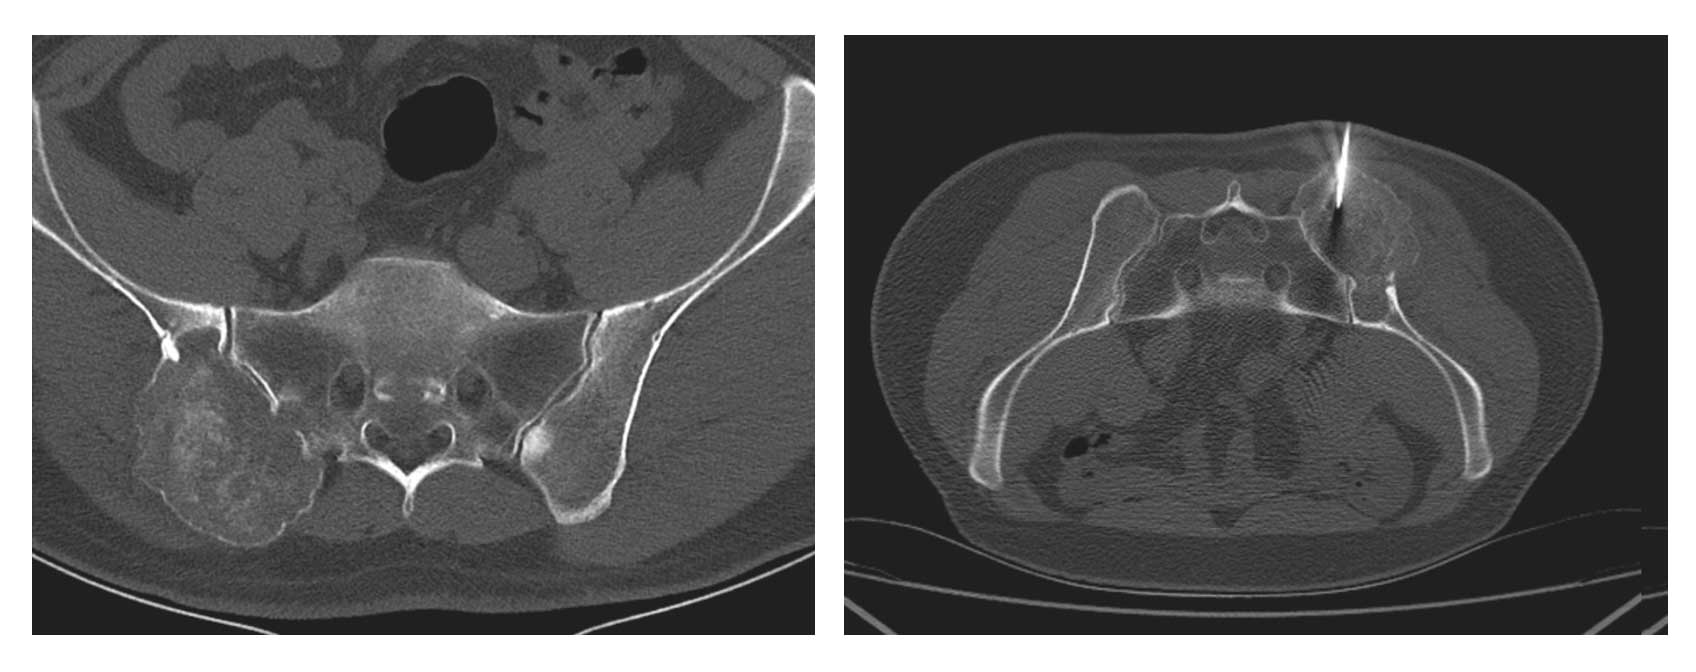

Ameliyat Öncesi: Tomografide sağ iliak kanat ve sakrum yerleşimli kemikte harabiyete neden olan tümör dokusu ve biyopsi iğnesi görülmekte.vaka 9 1